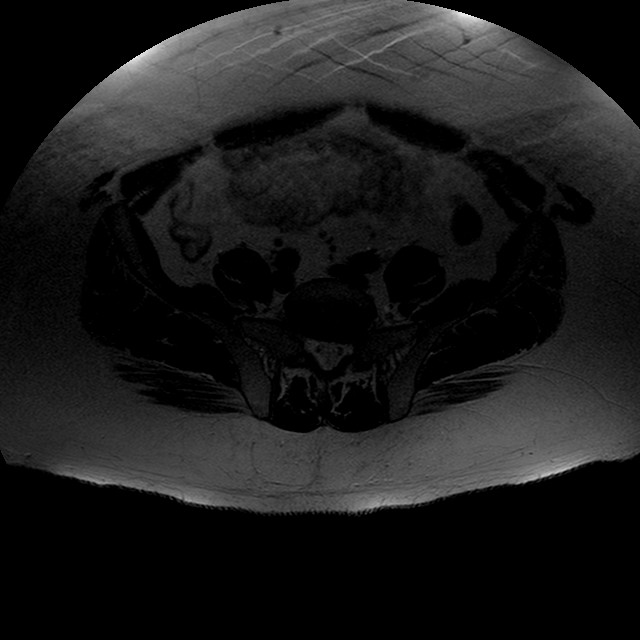

Esami: RMN BACINO

T2w TSE

Evidenti e simmetriche alterazioni osteofitosiche in regione coxo femorale con riduzione delle rime articolari. Degenerazione completa del cercine glenoideo. Non attuali segni di versamento articolare. Non segni di edema osseo che escludono attuale algodistrofia od osteonecrosi. Lieve e simmetrica riduzione del trofismo della muscolatura glutea.